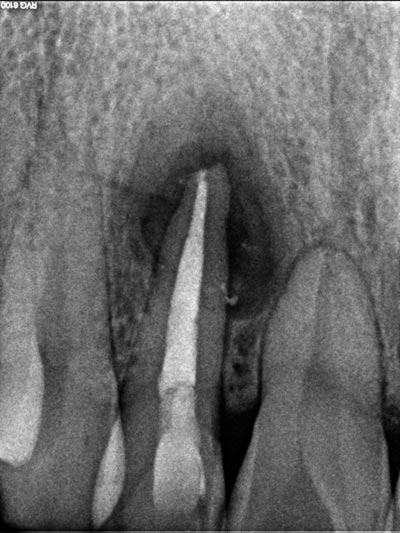

Imágenes:

Radiografía previa y final del tratamiento.

Medimos el ápice, retiramos el relleno anterior y colocamos relleno biocompatible.